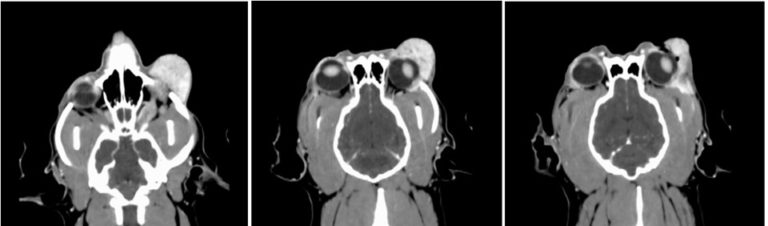

Computed Tomography with Contrast- Skull

Left lacrimal gland neoplasia such as adenocarcinoma is highest on the differential list.

The images below start just inferior to left globe. The first image shows the contrast enhancing mass can be seen causing dorsal elevation of the globe. The mass is seen wrapping around the lateral aspect of the globe and extending posteriorly in to the orbit.

For Leo Lambchop, the CT scan revealed a laterally placed tumor that wrapped posteriorly around the globe in the dorsolateral aspect of the orbit. The orbit of the dog is mostly enclosed in bone making access to retrobulbar disease challenging. Between the zygomatic process of the frontal bone and the frontal process of the zygomatic bone extends the fibrous, orbital ligament. Typically extensive disruption of surrounding musculature and osteotomies are needed for adequate exposure of the orbit.